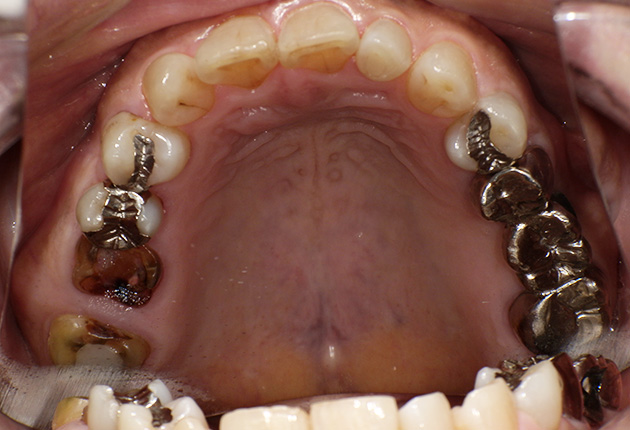

よく噛めず笑うと銀歯が目立つので気にされていました。

| 主訴 | ブリッジ脱離、しっかり噛めない |

| 診査診断 | 上顎歯牙欠損、歯周病、不良補綴、根尖性周囲炎。 不正咬合により噛み合わせのバランスが悪い事が原因により咬合治療が必要。 |

| 治療内容 | 欠損部インプラント 不正咬合に対し不良補綴のやり直しと合わせて咬合再構築 |

| 治療期間 | 4ヶ月 |

| 費用 | 200万円 |